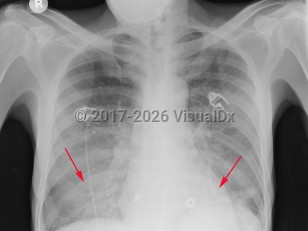

Pneumocystis jirovecii pneumoniaPneumocystis jirovecii pneumonia